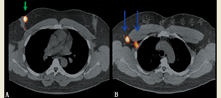

在识别SLNs方面,断层显像优于平面显像,因此在SLN方案中使用SPECT或SPECT/CT有重要价值[17]。对于头颈部黑色素瘤,SLNs可能会距原发肿瘤较近,SPECT或SPECT/CT或许有助于定位在平面显像时因邻近注射点而被掩盖的SLNs[18]。对于乳腺癌,SPECT/CT适用于以下情形,如未找到SLN、腋窝外淋巴结或内乳淋巴结显影、怀疑污染、患者体质量指数高、既往行乳腺手术或对侧摄取(图4)[19,20]。